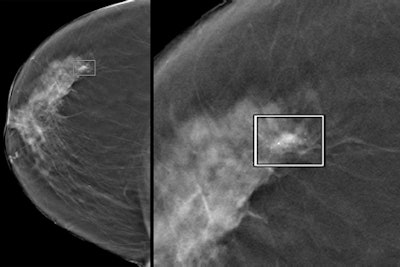

A new computer-aided detection (CAD) algorithm for digital breast tomosynthesis (DBT) studies delivers high sensitivity and an acceptably low false-positive rate, according to Italian researchers. In a retrospective study of nearly 200 women who underwent DBT for breast cancer screening, CAD demonstrated sensitivity of 89% with a false-positive rate of 2.7 per breast.

DBT is an improvement over digital mammography in its ability to improve visualization of masses and architectural distortions more effectively and efficiently, they noted. It also diminishes the masking effect of superimposing glandular tissues. However, the fast-emerging modality may also present unique challenges for interpreting some lesions.

"Early reports showed that DBT might not be as effective for the detection of microcalcification clusters as it is for masses," making the search for microcalcification clusters more difficult and time-consuming than with digital mammography.

Of the lesions detected, 62 of 72 were masses, 20 of 22 were microcalcifications, the authors wrote. Specifically, the CAD algorithm found 37 of 39 microcalcification clusters (95% sensitivity) and 79 of 89 masses (89% sensitivity), including 17 of 17 masses with calcifications. On average, 0.5 false positives per view were microcalcification clusters, 2.1 were masses, and 0.1 were masses and calcifications, the group reported.

Mass margins are more clearly visible in DBT, but its 3D nature and the presence of artifacts due to acquisition angle complicates segmentation of both masses and calcifications. Processing 3D volumes also tends to create large numbers of false positives.